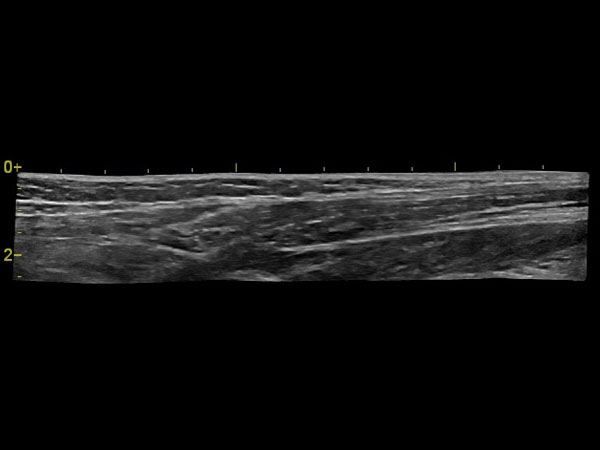

Панорамное сканирование:

Да